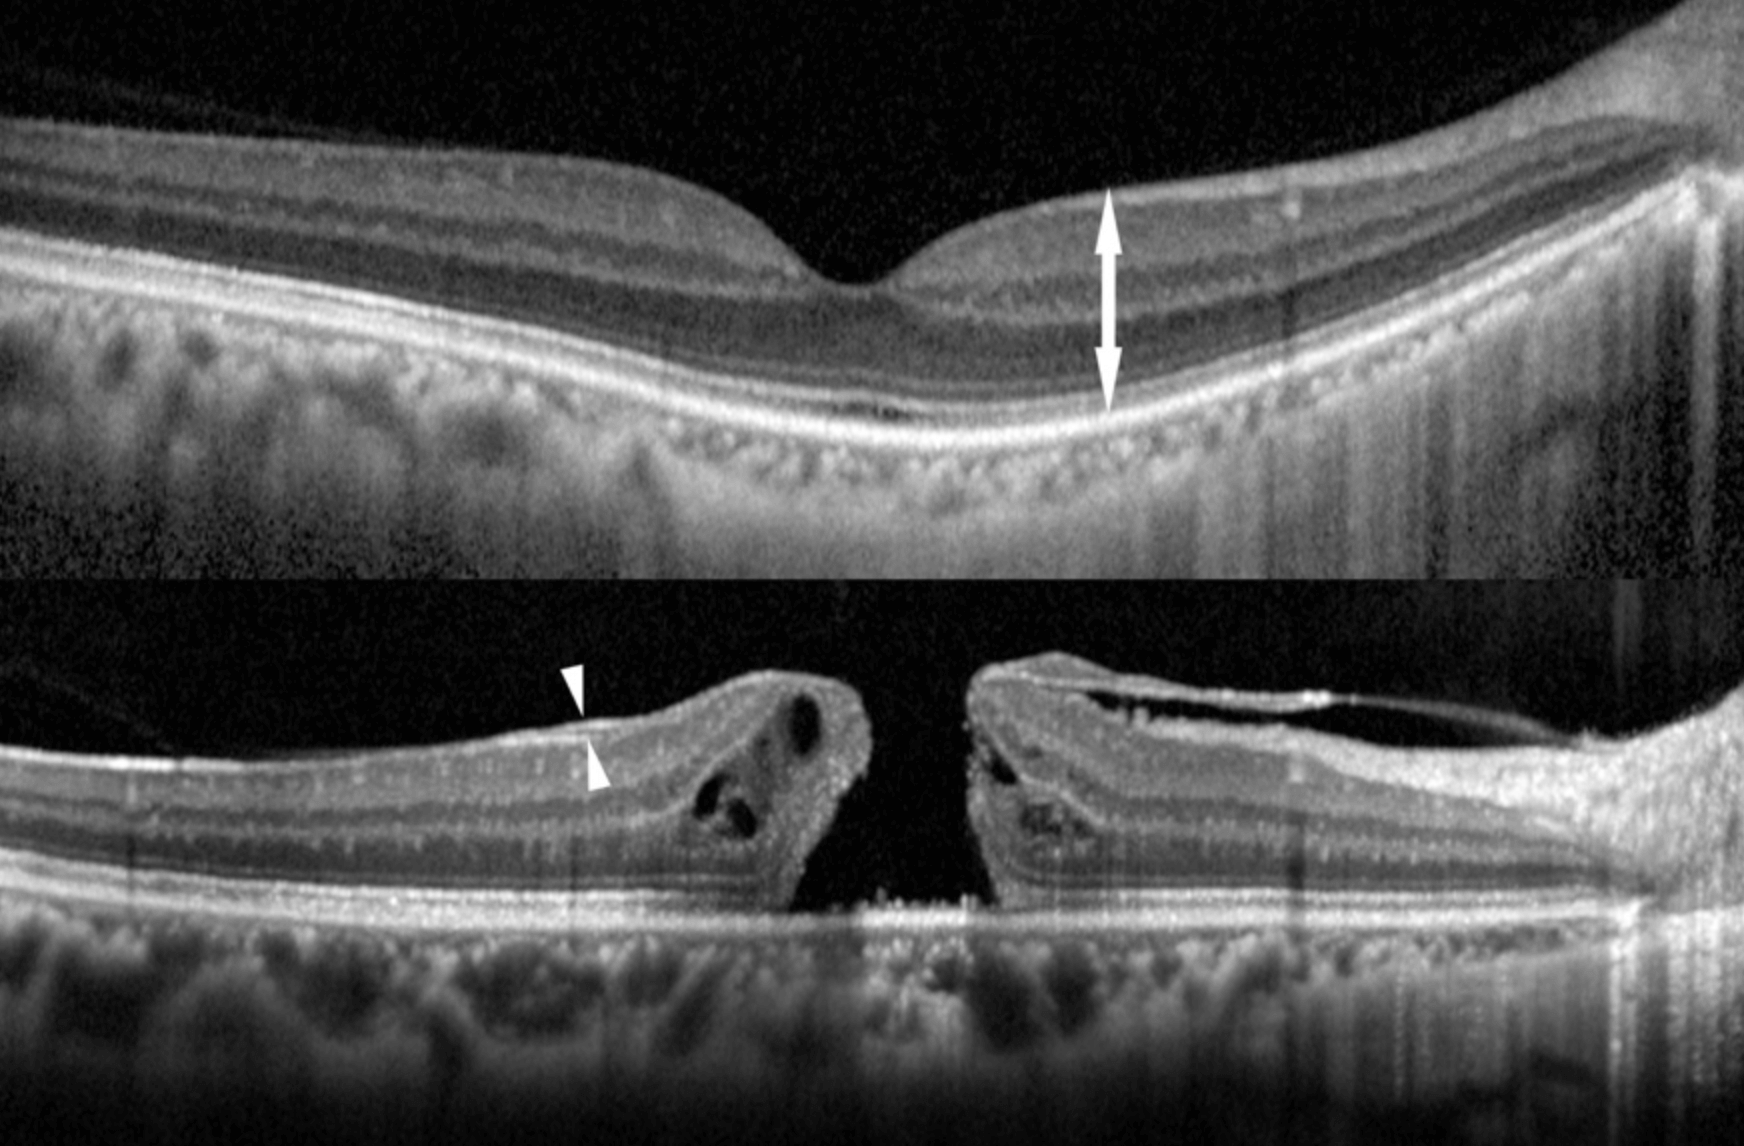

망막전막 수술은 망막전막과 망막앞의 후방 유리체를 수술로 절제합니다. 그런다음 망막전막과 내경막을 제거하고, 주위에 구멍이 있는경우 레이저로 광응고를 수행합니다.

자각 증상이 가벼운 경우에는 경과 관찰을 실시하고, 질병이 진행되어 물건의 왜곡이 강해지거나 시력이 저하된다는 증상으로 일상생활에 지장이 나오는경우 유리체 수술을 실시 할수 있습니다.

망막전막의 초기에는 자각증상이 없기 때문에, 우연히 건강검진이나, 안과 검진을 통해 발견됩니다. 질병이 진행되면 막이 두꺼워지고 줄어들기 때문에 망막에 주름이 생깁니다. 이렇게 망막에 주름이 생기면 물체가 왜곡되어 보이거나, 트게 보일수 있으며 시력의 저하가 발생할수 있습니다.